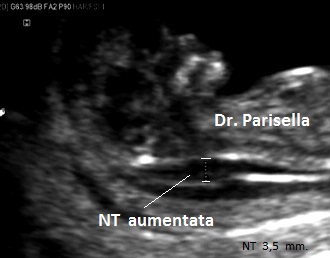

E' una displasia scheletrica caratterizzata da nanismo rizomelico con incurvamento del femore e della tibia. Si associano dismorfismo facciale (con micrognazia e palatoschisi), ipoplasia toracica  con coste corte (di solito sono presenti 11 paia di coste), ambiguità dei genitali fino al sex reversal (cariotipo maschile con fenotipo femminile); frequente è l'ipoplasia della fibula; si evidenzia inoltre piede torto, idrocefalia, macrocefalia.

Dal punto di vista diagnostico la caratteristica più importante e significativa è infatti l'incurvamento del femore e della tibia; una caratteristica unica, ricorrente nel 75% dei feti affetti, è la presenza di un cariotipo di tipo maschile con genitali ambigui o femminili.